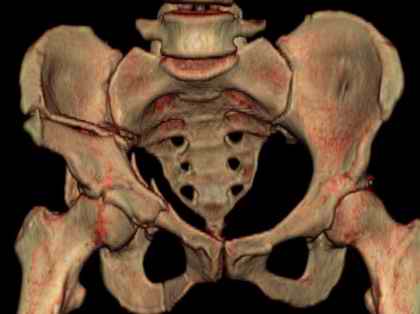

Посылаю схемы и 3D реконструкцию подобного повреждения. Называется он полным высоким двухколонным переломом вертлужной впадины, а "переломы крыла и тела подвздошной кости" входят в это понятие.

Вариантов остеосинтеза много (можно и не оперировть, т.к. конгруентность при таких переломах как правило сохраняется)

1 закрытая репозиция аппаратом + фиксация через проколы винтами

2 закрытая репозиция передней колонны + открытая задней колонны из задне-неружного доступа

3 открытая репозиция передней колонны из подвздошнго доступа + открытая задней колонны из задне-наружного доступа

4 открытая репозиция из илиоингвинального доступа

5 открытая репозиция из Y образного доступа

Я бы ориентировался на Y образный доступ

или из двух если есть сомнения в целостности задних отделов крыла.

прикладываю схему доступа и случай.

Одним задне наружным переднюю колонну не достать, а илио-ингвинальный более сложный не позволяет контролировать суставную поверхность и трудно управлять задней колонной.